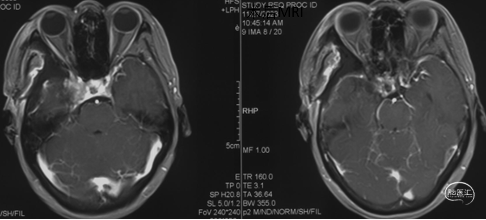

术前影像学检查

头颅MRI+增强